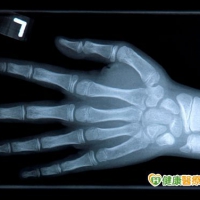

(健康醫療網/關嘉慶報導)每個家長都希望孩子長的像大樹一樣,期盼孩子長的高又壯;至於孩子可以長多高呢?小兒科醫師指出,孩子未來能長多高最準確的估算方式是骨齡,只需要照一張左手的X光片,就能檢測。

小兒科醫師丁綺文表示,影響身高原因遺傳佔70%,後天努力佔30%;目前已知有24個基因變異位點與身高潛能有關,經過基因檢測可以估算成年身高,然而,最準確的估算方式是骨齡,只有骨齡才可以看出先天和後天的共同影響,骨齡才是內在真正的年齡。

檢測骨齡方法竟只需要照一張左手的X光片,就能算出孩子成年後能長到多高;丁綺文醫師指出,因為手掌是身體中擁有最多骨骼的部位,包括手指骨、掌骨、腕骨共27塊骨頭,根據這些骨頭的成熟度,就能估算骨齡,且可以了解生長板何時會關閉,即可據此算出「預估成年身高」。

丁綺文醫師進一步解釋,骨齡會受到生長激素和性荷爾蒙作用而變動,青春期的孩子發育成熟速度不同,就都會表現在骨齡;性荷爾蒙量多的孩子,骨齡可能一年增加1.5歲到2歲。

所以,丁綺文建議,女孩滿9歲,男孩滿10歲,就應該照X光檢測第一張骨齡,才能了解孩子是否提前或落後發育,之後每年定時照一張,直到青春期結束,生長板關閉;平常並應早睡、多運動、多吃含有胺基酸的食物,讓遺傳潛能充分發揮,就能達到理想的成年身高。